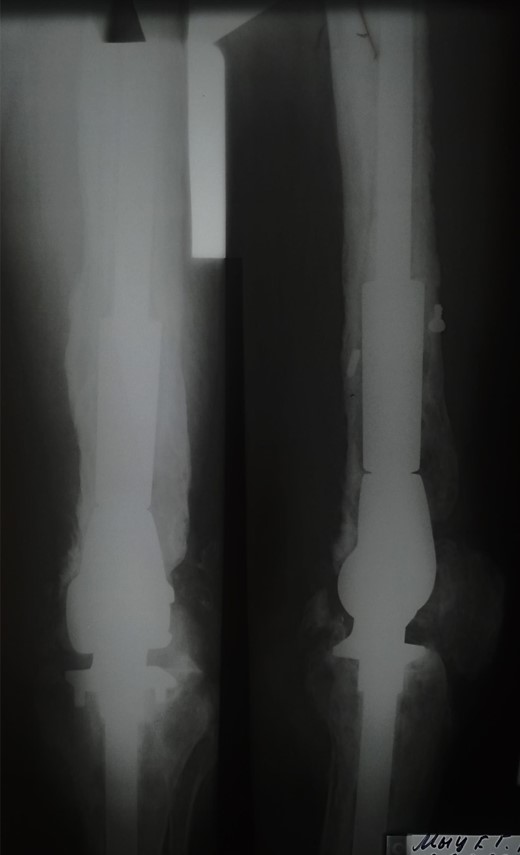

Приклад 3. Хвора К. 52 років. Діагноз: Деформівний IVст. гонартроз, стан після ТЕП лівого КС (2013р.). ІМТ хворої складає 35 балів. Асептична нестабільність компонентів ендопротеза лівого колінного суглоба, міграція великогомілкового компоненту (2017 р.) (рис. 2 а). Хворій виконано ревізійне ендопротезування: видалення компонентів ендопротезу, виявлений дефект медіального виростку великогомілкової кістки тип Т3А за класифікацією АОRI [G.A. Engh, C.H. Rorabeck, 1997]. Під час операції виконана кісткова пластика дефекту. Використаний ендопротез колінного суглоба з подовжувачами.